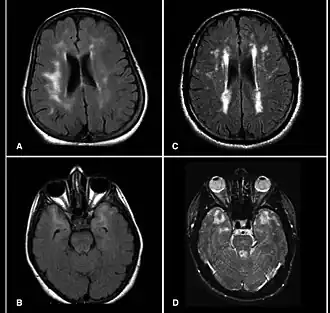

Description de cette image, également commentée ci-après

IRM cérébrale montrant des lésions et lacunes ischémiques multiples chez un patient atteint de CADASIL.

IRM

L'IRM est l'examen de choix, elle montre des hyperintensités confluents de la substance blanche[11]. Des lésions hyperintenses plus circonscrites sont également observées dans les noyaux gris centraux, le thalamus et le pont[12].

Bien que la substance blanche sous-corticale peut être diffusément impliquée, initialement la maladie implique surtout le lobe antérieur temporal (86%) et la capsule externe (93%). Il y a une épargne de la substance blanche sous-corticale occipitale et orbitofrontale[11].

Des micro-hémorragies cérébrales ont été démontrées dans environ 45% (intervalle de 25-70 %) des cas[13].

Finalement, l'atrophie cérébrale se développe, ce qui est bien corrélée avec le degré de déclin cognitif.